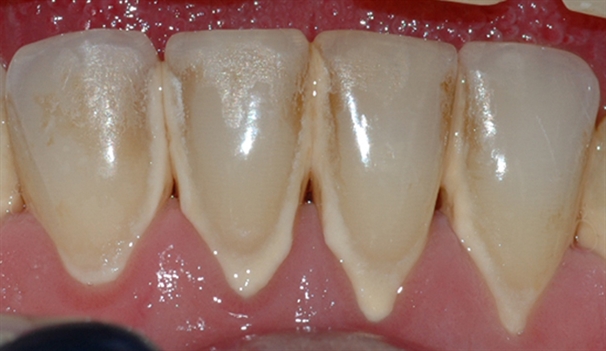

Bildet viser tilsynelatende normale tannkjøttsforhold ved tenner i underkjeven.